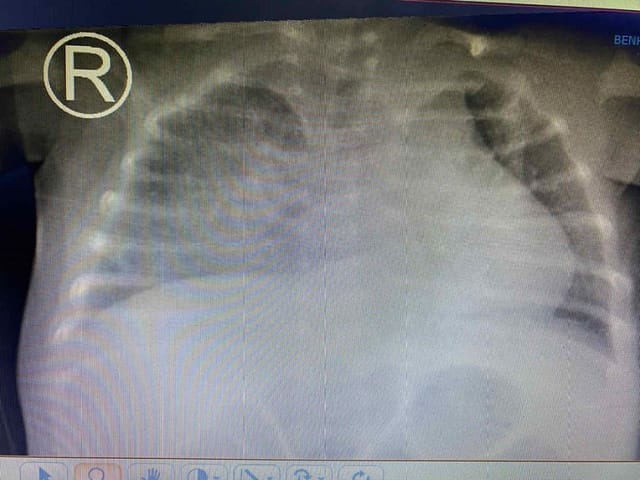

Tình trạng hô hấp diễn tiến xấu hơn, em thở mệt co kéo, SpO2 80-82%. Được chuyển thở máy không xâm nhập nhưng tình trạng vẫn không cải thiện, hình ảnh Xquang phổi cho thấy tổn thương phổi nặng lan tỏa 2 bên, biểu hiện hội chứng suy hô hấp cấp tiến triển (ARDS) nên được đặt nội khí quản thở máy.